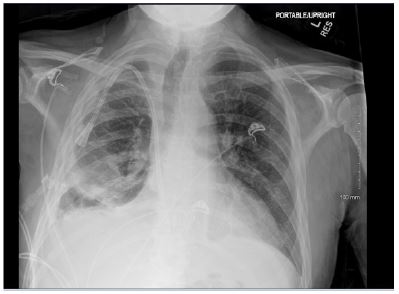

Patient presented with elevated blood pressure at 174/88. BMP was significant for Na 133, K 4.6, BUN 29, Cr 5.3. CMP is significant for Albumin 2.5. CBC was significant for Hb 8.7, Hct 25.0. D-dimer was found elevated at 4,670. PT and INR were normal. ABG significant for pH 7.52, pCO2 31.4, HCO3 25.3. A chest x-ray on admission demonstrated a large right-sided pleural effusion, contributing to significant compressive atelectasis of the right lung and leftward deviation of the mediastinal structures. Thoracentesis was performed, which demonstrated blood- tinged serosanguinous fluid. Transthoracic echocardiogram demonstrated EF 60-65%, LV diastolic dysfunction, with trace mitral and tricuspid regurgitation, and was negative for pericardial effusion. CT Chest demonstrated a large volume right-sided pleural effusion without pneumothorax, with extensive progressive atelectasis throughout the right lung. There was also a trace left-sided pleural effusion and pleural thickening with round atelectasis in the posterior left lower lobe, as well as minimal interstitial edema in the left lung. A chest tube was placed with consistent drainage throughout admission. Repeat chest x-rays continued to demonstrate pleural effusion. Thoracotomy, decortication, and pleurodesis were performed with Video-Assisted Thoracoscopic Surgery (VATS), with significant improvement of symptoms. The pleural fluid biopsy was negative for malignancy and revealed fibrocollagenous tissue with chronic inflammation and a few reactive epithelial cells. Thorough review of the patient’s medication list led to suspicion that the patient’s 50 mg Hydralazine three times a day may be the offending agent. Anti-histone antibody titers were found to be elevated at 3.7. Free Kappa and Lambda light chains were elevated. Antinuclear Antibody (ANA) titers were found to be negative. Hydralazine was discontinued, and after chest tube removal and improved chest x-ray, the patient was discharged home. It was recommended that the patient follow up with their primary care provider and rheumatologist.

Figure 3: Chest radiographs obtained post-VATS and prior to discharge. Compared to initial presentation, there is marked interval improvement with resolution of the large right pleural effusion and re- expansion of the right lung.